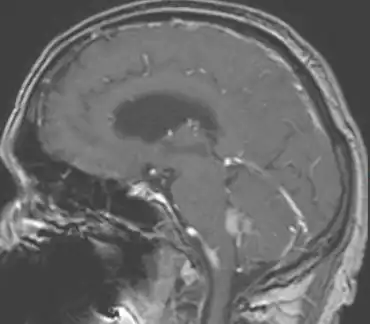

.png)

In terms of the diagnosis of Choroid plexus carcinoma the use of magnetic resonance imaging helps in the evaluation.[9]